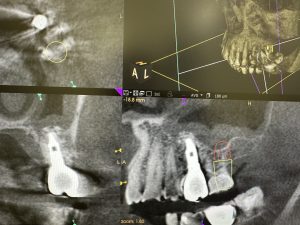

右側は約14年経過、安定している💪

赤印はスプラインツイスト

青印は、エニーリッジ